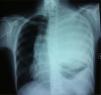

Case ReportA 19-year-old patient was admitted to our hospital for pain in the left arm. She presented no other symptoms. Both the physical examination and anamnesis were anodyne. Plain chest radiography revealed an extensive opacity that occupied almost the entire left hemithorax and caused a deviation of the trachea and the mediastinum towards the right (Fig. 1). Afterwards, computed tomography (CT) exploration better defined this lesion and revealed a solid heterogeneous mass that measured 16cm×15cm×15cm (Fig. 2). The mass extended to the left supraclavicular region, with no skeletal destruction. It was characterized by smooth edges and it demonstrated a direct relationship with the mediastinal vascular structures, without obliterating them. The left lung was completely collapsed. After CT, the patient underwent magnetic resonance imaging (MRI) for more detailed evaluation. The mass originated at the posterior mediastinum, where it manifested low signal intensity in T1 and high signal intensity that was heterogeneous in the weighted MR images in T2, and, after the administration of gadolinium (0,1mmol/kg), an intense contrast was demonstrated. We considered that the lesion may possibly have been a lymphoma or, although less likely, a primary lung carcinoma as an initial diagnosis. Positron emission tomography –computed tomography (PET-CT) was ordered, which revealed increased fluorodeoxyglucose (18FFDG) uptake by the mass. For the definitive diagnosis, a biopsy was taken by CT-guided transthoracic needle aspiration. The histopathologic exam revealed layers of small, round, blue cells with small round nuclei and limited cytoplasm. Immunohistochemistry demonstrated positive staining for CD99 and vimentin. It was negative for all lymphoma markers, including CD31, CD34, CD45, desmin and cytokeratins. Given these findings, the mass was diagnosed as an EES. Immediately afterwards, we consulted with the thoracic surgery department and an intervention was programmed to resect the lesion.